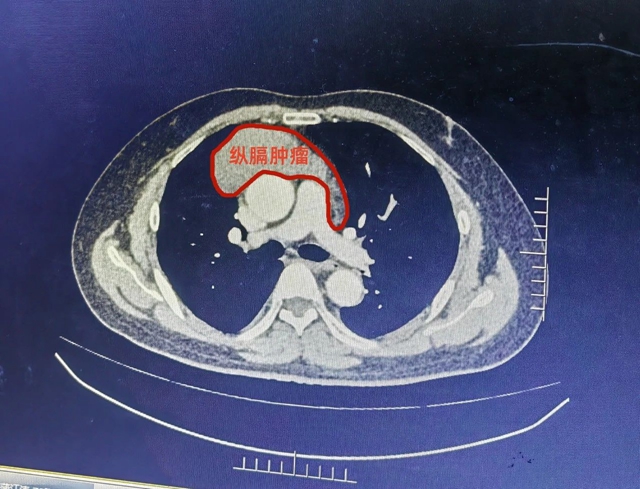

近日,杨先生突然出现右侧胸痛,于当地医院初诊后,遂至西南医科大学附属医院胸外科进一步就诊,诊断为纵隔肿瘤,经CT显示其肿瘤直径达12公分,为巨大纵隔肿瘤。

同时,因胸腔纵隔内位置特殊,生长在心脏主要血流通道——动、静主动脉表面,骑跨两侧胸腔,肿瘤又达12公分之大,手术操作稍有闪失,便可能引发心脏大血管大出血,导致患者生命危险,进一步加大了手术难度。再加上患者本身又患有高血压,这也是外科手术发生出血风险的高危因素之一。